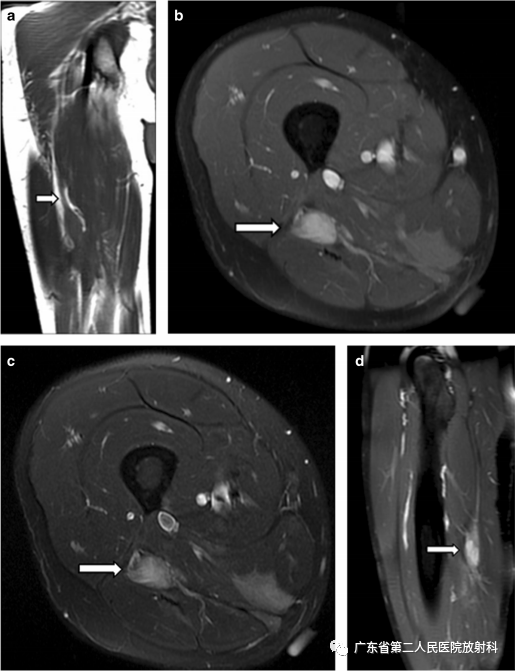

参考病例

一名23岁男性,右坐骨神经弹道创伤后状态,组织学证实有端球神经瘤(EBN)